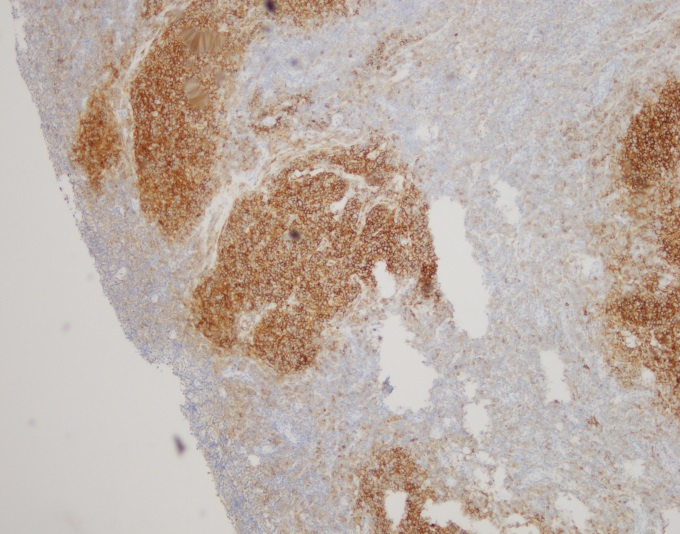

By immunohistochemistry, the neoplastic cells are immunoreactive for CD20 and BCL2. BCL2 is brighter in the vague nodular areas which are also highlighted by CD10 and BCL6. CD23 is variably positive in a large subset of cells. MUM1 is negative. CD21 highlights the enlarged and irregularly shaped follicular dendritic cell meshwork present in the areas with nodules. CD3 and CD5 highlights admixed T-cells. The proliferation index by Ki-67 is low and approximately 10%.

Cytogenetic analysis using fluorescent in-situ hybridization performed on paraffin embedded sections revealed numerous cells with an IGH/BCL double fusion probe signal pattern consistent with IGH/BCL2 gene rearrangement.

Overall, the morphologic and immunophenotyipic findings in conjunction with the cytogenetic results are in keeping with involvement by a B-cell lymphoma most consistent with a follicular lymphoma. The follicles present contain <15 centroblasts per hpf and the low proliferation fraction makes it most compatible with a low grade (WHO morphologic grade 1-2/3) follicular lymphoma.

Making the diagnosis of follicular lymphoma involves assessing the H & E slides for follicular architecture, characteristic immunostains including positivity for BCL2 within follicles and the typical t(14;18) IGH/BCL2 translocation, which occurs in 90% of cases. 2